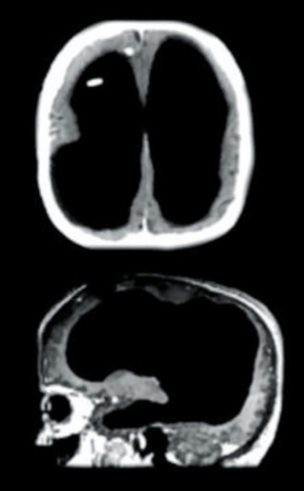

Mayor controversia, si cabe, es la que sigue levantando aún hoy la de un alumno de la Universidad de Sheffield, en Reino Unido. Acudió a un médico y profesor de la Universidad, el doctor John Lorber, porque le dolía la cabeza. Y al ver que la tenía algo más grande de lo normal, el doctor, presa de la curiosidad, quiso averiguar la razón y le hizo un escáner. Lo que Lorber no se esperaba era ver una cabeza prácticamente llena de líquido cefalorraquídeo en lugar de una masa gris con cerca de 10.000 millones de neuronas. Este alumno, con un coeficiente intelectual en la frontera de la genialidad, 140, mostraba un cuadro crónico de hidrocefalia que le había borrado casi por completo el cerebro. Sin embargo, pudo licenciarse en Matemáticas.

El escáner de John Lorber al estudiante de la Universidad de Sheffield.